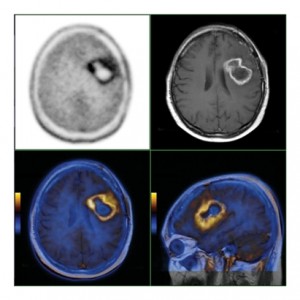

yorumsuz 12 sene önceBeyin Tümörlerinde PET / CT Nasıl Kullanılır?